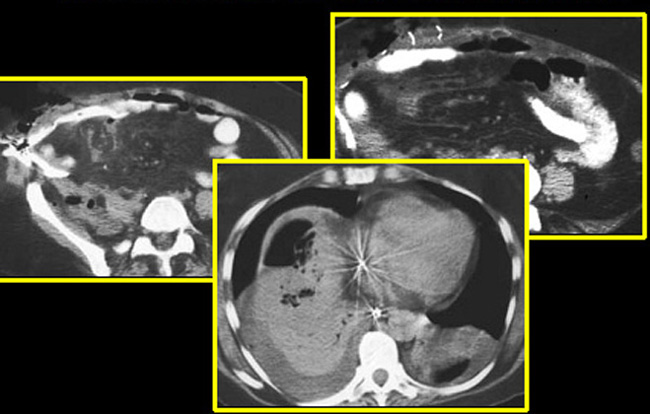

Subdiaphragmatic abscess post splenectomy

• Arrow points to multiloculated thick walled fluid collection in the left upper quadrant of the abdomen.

• Note absence of spleen.

Pancreatic abscess

Diffusely enlarged pancreas with air pockets.

Arrow points to body of Pancreas

Abscess is in tail of Pancreas